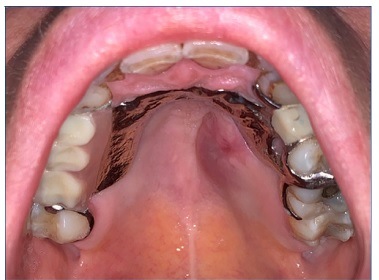

A doente iniciou tratamento com imuno‑quimioterapia segundo o protocolo R‑CHOP (rituximab, ciclofosfamida, doxorrubicina, vincristina e prednisolona), durante 6 ciclos. No fim do 3.º R‑CHOP foi possível observar a total regressão da lesão do palato (Figuras 9 e 10). A doente completa os 6 ciclos de quimioterapia com resposta completa e prossegue tratamento com rituximab de manutenção a cada 2 meses, durante 2 anos.

Figura 9 Regressão total da lesão anteriormente observada hemi‑palato (com prótese removível esquelética)

Figura 10 Regressão total da lesão anteriormente observada hemi‑palato (sem prótese removível esquelética)